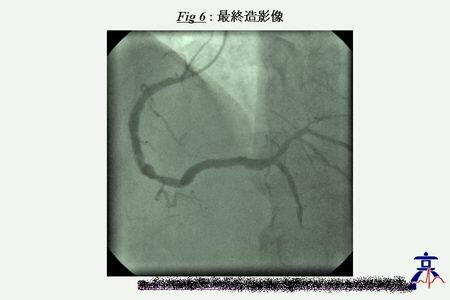

昨日の症例の画像を添付しましたので、ご参照ください。

LCA(LAO)

LCA(RAO)

RCA

DSA

LMTも入口部のみtightで、

bodyはそこそこの径があります。ただ、aortaの石灰化が強く、両方の入口部にも強

い石灰化があります。stentingする際には、stentの拡張不十分や、上行大動脈の縦

割れには要注意と思われます。頚動脈病変については、エコーで見る限り、石灰化の

強い病変で、soft plaqueではありませんでした。